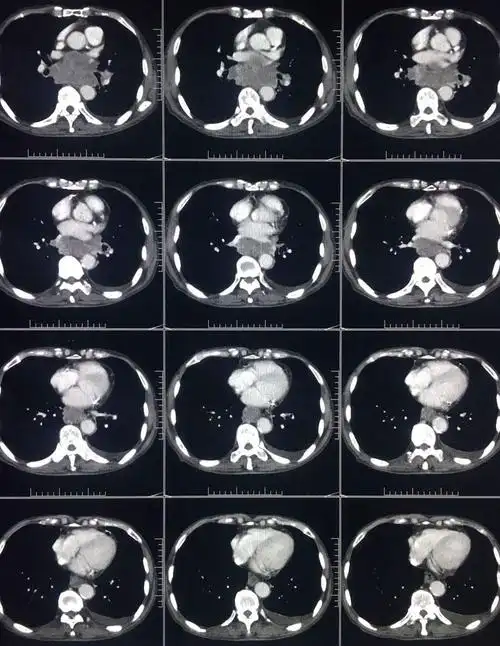

ct平扫 三期增强,这个纵隔占位有点难 [病例帖]